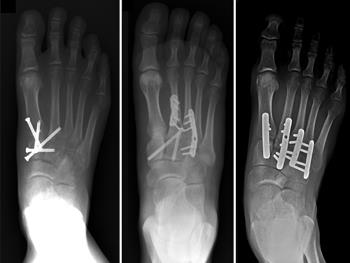

Fusion for Lisfranc Fracture

Radiographs showing a complete midfoot dislocation (left) before and (right) 2 years after fusion.

Reproduced with permission from Watson T, Shurnas P, Denker J: Treatment of Lisfranc Joint Injury: Current Concepts. J Am Acad Orthop Surg 2010; 18(12):718-728.